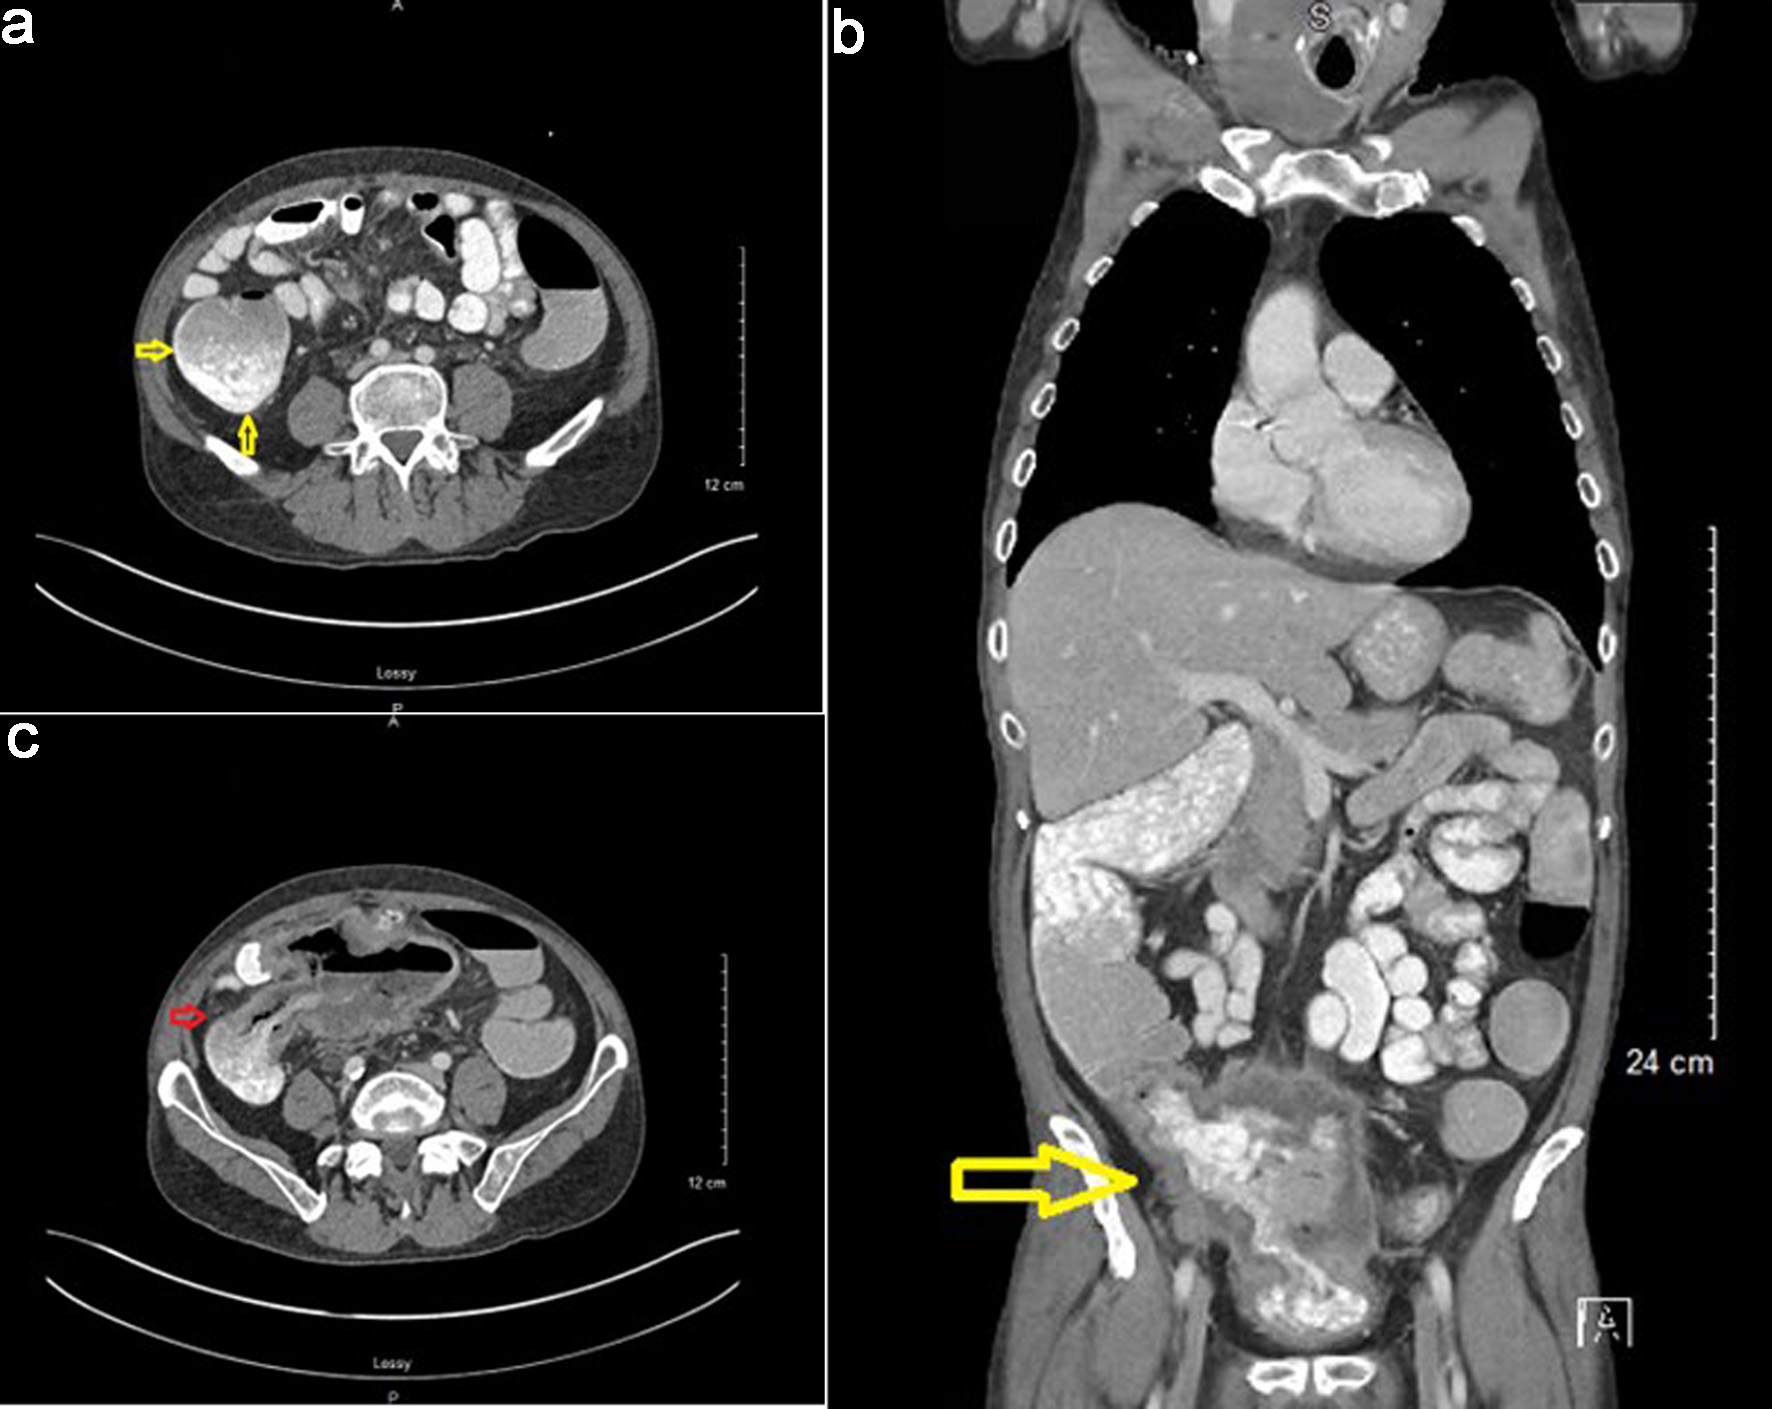

The patient was then hospitalized for severe diarrhea due to Clostridium difficile colitis and was treated with vancomycin. During this hospitalization, a CT scan of the abdomen with an oral and intravenous contrast was obtained. This revealed a markedly distended cecum with thick-walled changes (Fig. 9a), significant inflammatory stranding, and overt fistulization to the bladder. Dense oral contrast material was noted within the bladder (Fig. 9b, c). Unfortunately, due to the mass effect and colovesical fistula, the patient developed obstructive uropathy, necessitating the placement of a right-sided nephrostomy tube. He developed a urinary tract infection with E. coli as well, which was treated with antibiotics.

Click for large image

Figure 9. Computed tomography (CT) scan with oral and IV contrast findings. (a) Markedly distended cecum with thick-walled changes (arrows). (b) Oral contrast noted in bladder indicating a presence of a colovesical fistula (arrow). (c) Dense oral contrast material traversing colovesical fistula (arrow).